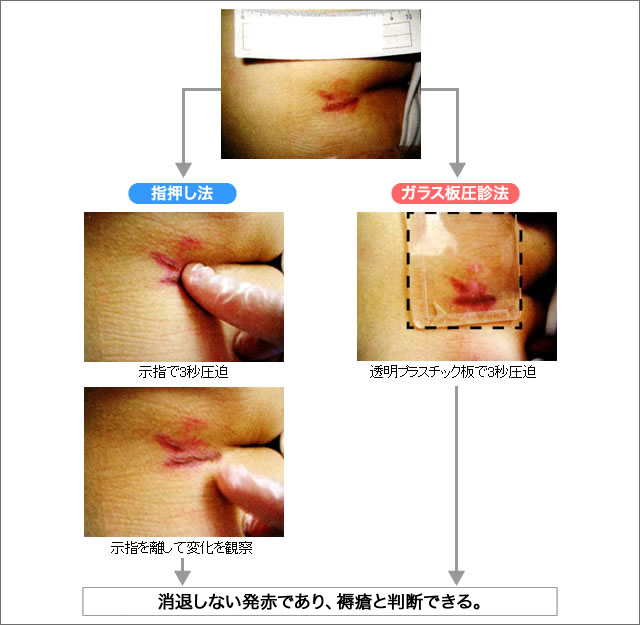

皮膚の観察褥瘡辞典 for MEDICAL PROFESSIONAL医療関係者向け情報マルホ株式会社。

皮膚の観察褥瘡辞典 for MEDICAL PROFESSIONAL医療関係者向け情報マルホ株式会社。